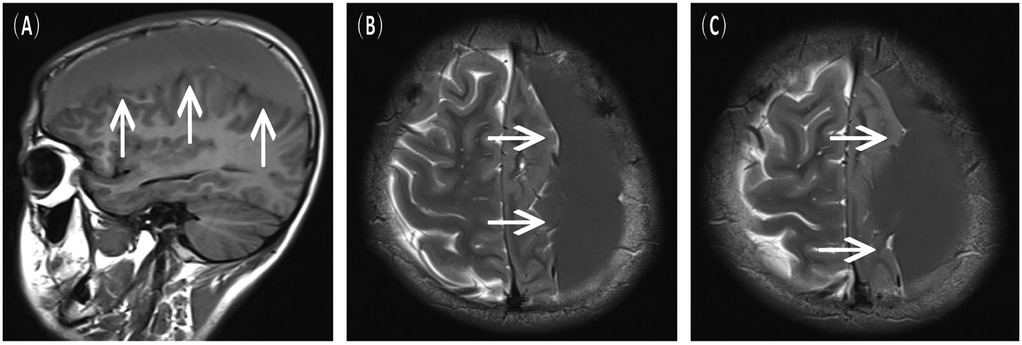

A 16-year-old male presented to the hospital with a 10-day history of episodic headache. Three years earlier, he had been evaluated for headache, and magnetic resonance imaging (MRI) identified an arachnoid cyst in the left fronto-temporo-parietal region (Figure 1). Given the absence of significant mass effect or neurological deficits and the resolution of symptoms, surgical intervention was not advised at that time. No specific intervention was performed, and the headache subsequently resolved on its own. No further imaging studies were conducted thereafter. Ten days ago, the patient experienced recurrent headaches without apparent cause or trigger, characterized by episodic attacks predominantly localized to the left occipital region. The headache was initially relieved by oral painkillers but reappeared 2 days before admission to the hospital, worsening compared to the previous episode. For further evaluation and management, the patient presented to our institution. An outpatient magnetic resonance imaging (MRI) revealed a massive chronic subdural hematoma (CSDH) in the left fronto-temporo-parietal region (Figure 2). No computed tomography angiography (CTA) or digital subtraction angiography (DSA) was performed at this time. The patient underwent burr-hole irrigation and drainage of the CSDH under general anaesthesia. Concurrently, the cyst wall was fenestrated to establish communication between the cyst and the extracerebral space. Postoperative imaging confirmed complete resolution of the hematoma and a significant reduction in the size of the cyst (Figures 3A–C). His headaches were relieved significantly compared with those of the previous day. The cyst did not recur on the patient's return visit 6 months after the operation (Figures 3D–F), and no symptoms such as headache were observed during the 6 months.

Figure 2. Preoperative MRI scans upon the current admission, indicative of a left chronic subdural hematoma. (A) Sagittal view, T1-FLAIR sequence. (B,C) Axial view, T2-weighted sequence.